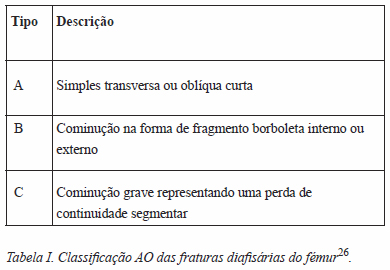

As radiografias foram revistas por três autores (DS, MF e PC) para classificação do padrão de fratura segundo a classificação AO (Tabela 1)26.

No grupo CB, as fraturas foram classificadas como A (fratura simples transversa ou oblíqua curta) em 7 casos e como B (cominução na forma de fragmento borboleta interno ou externo) em 2 casos. (Figura 1) No grupo SB, as fraturas foram classificadas como B em 2 casos e como C (cominução grave representando uma perda de continuidade segmentar) em 5 casos.

A classificação das fraturas por 3 autores diferentes, usando a classificação AO, mostrou que as fraturas no grupo CB eram fraturas compatíveis com o padrão de insuficiência definido pela ASBMR (7 tipo A e 2 tipo B da classificação AO), em doentes com boa reserva óssea em termos radiográficos. Este achado contrasta com as características radiológicas observadas no grupo SB, em que se observou uma maior cominução e desorganização das fraturas.